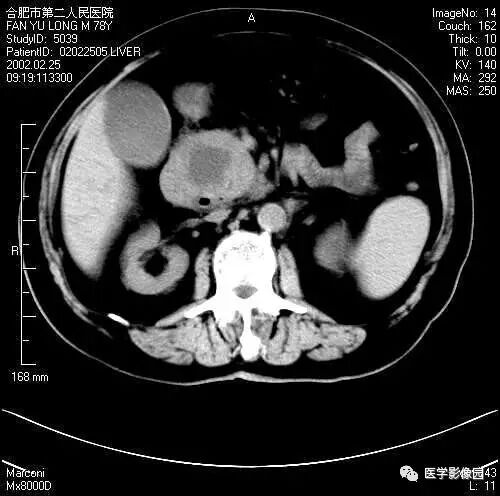

图6-4-10胰腺癌

A.CT平扫胰头球形扩大,

其内呈低密度(↑);

B.增强扫描动脉期,

胰头癌低密度显示更清晰